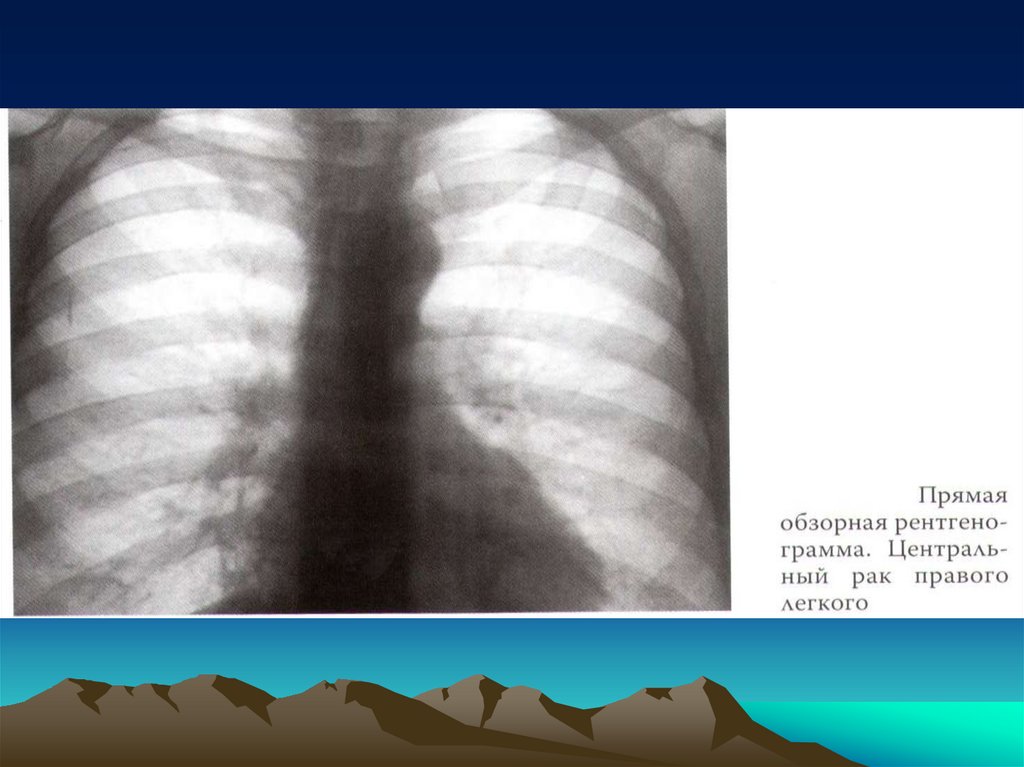

Центральный рак легкого

Кашель

Кровохарканье

Повышение температуры тела

Одышка

Лихорадка и продуктивный кашель

Боль